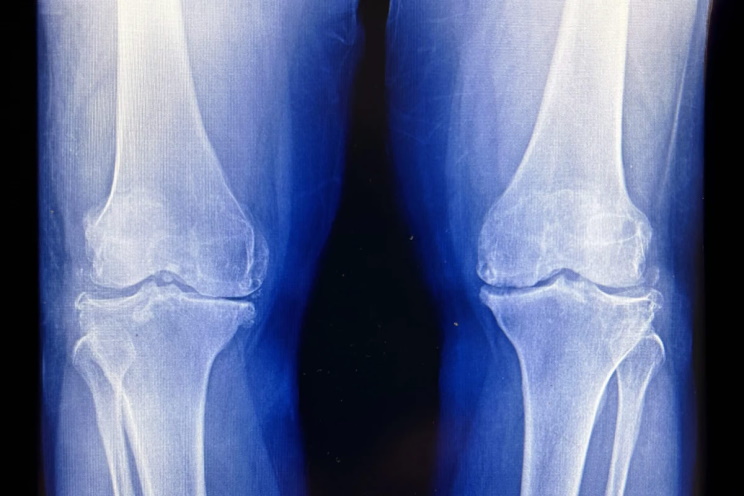

В Южной Корее учёные доказали пользу малых доз радиации для помощи людям с тяжелым остеоартрозом коленей

В Южной Корее учёные доказали пользу малых доз радиации для помощи людям

с тяжелым остеоартрозом коленей

Группа корейских ученых привлекла 114 добровольцев с первичным остеартрозом коленного сустава. Диагноз всем им ставился по рентгеновским снимкам и наличию существенной боли при ходьбе. Участников разбили на три группы: первой колени облучали сверхмалыми дозами радиации (шесть сеансов по 0,05 грея), второй — малыми (то же число сеансов по 0,5 грея), третью не облучали ничем. Вторая группа получила локальное облучение, сравнимое с 30 000 рентгеновскими снимками груди или 420 компьютерными томографиями грудной клетки. О результатах исследователи отчитались на ежегодном собрании Американского общества радиотерапии.

Никто из участников не мог принимать на регулярной основе опиоидные болеутоляющие или нестероидные противовоспалительные препараты в первые четыре месяца после процедур (или их имитации у группы плацебо). Затем ученые сравнили отзывы членов разных групп о своем состоянии. Среди тех, кто получил максимум облучения, об улучшениях заявили 70% участников, в группе плацебо — только 42%. Клинические серьезные улучшения в смысле силы боли и функциональности коленных суставов в группе максимального облучения зарегистрировали у 57% участников. Среди получателей плацебо-лечения — только у 31%.

Для тех, кто получил лишь 0,3 грея, ситуация была промежуточной: 58% заявили об улучшении состояния, но вот клинические серьезные улучшения по сравнению с группой плацебо врачи не зафиксировали. Как и участники двух других групп, получатели плацебо не имели изменений в составе крови или в уровне маркеров воспалительных процессов. Никаких побочных эффектов от лечения найти не удалось. Это отличает картину от радиотерапии при раке, где локальные дозы в десятки раз выше трех грей и без побочных эффектов сложно обойтись.

Авторы научной работы продолжили отслеживать состояние облученных, сейчас идет 12-месячный цикл мониторинга. По его итогам запланировали публикацию. Как отметили разработчики метода, он не сможет регенерировать хрящевую ткань в коленном суставе, если она уже утрачена. Но пока речь идет об умеренной или средней силе остеоартроза, такой подход способен серьезно замедлить развитие болезни.